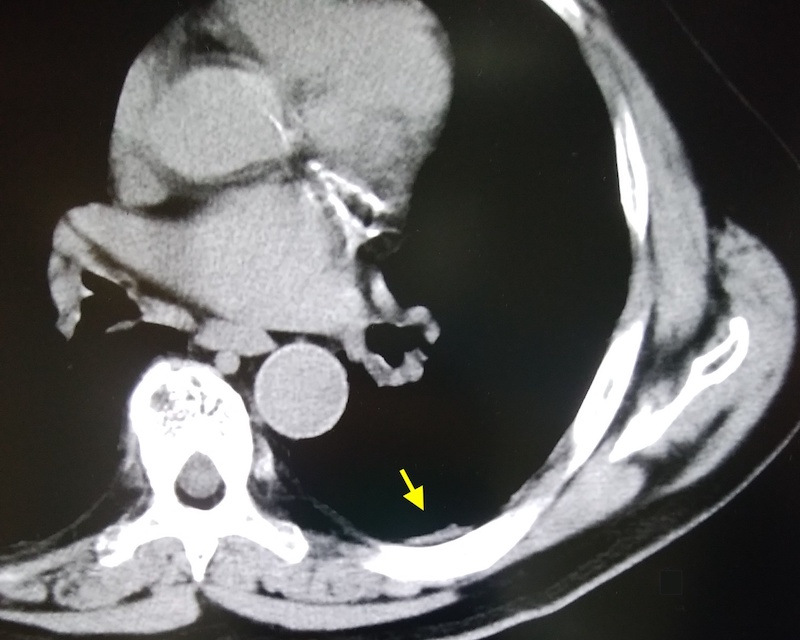

胸部エックス線で胸膜プラークは見えない。胸部CT写真を撮影したところ、見えにくい横隔膜に石灰化した胸膜プラークを見つけたボイラー工の事例。

写真3 ボイラー工66歳初診時エックス線所見(ー)

写真4 66歳のCT所見(あり)